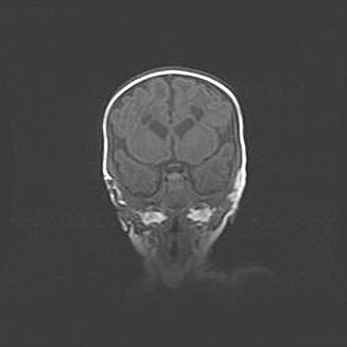

Наружная гидроцефалия с возможной атрофией височных областей.

Возраст: 28 дней

Вес: 3670 г

Пол: мужской

Окружность головы: 38 см

Срок гестации: 40 недель

Гидроцефалия головного мозга у новорожденных – это заболевание, которое характеризуется скоплением избыточного количества спинномозговой жидкости в желудочковой системе головного мозга в результате затруднения её перемещения от места выработки к месту поглощения в кровеносную систему или вследствие нарушения абсорбции. При открытой наружной форме гидроцефалии у новорожденных расширяются и переполняются субарахноидные пространства.

При нормотензивных  формах,  которые,  как  правило,  являются  следствием  перенесенных ишемических  повреждений  паренхимы  мозга,  возможно  сочетание микроцефалии  с нормотензивной гидроцефалией. В основе данных изменений лежит атрофия больших полушарий с преимущественной  локализацией  в  лобно-височных  областях.